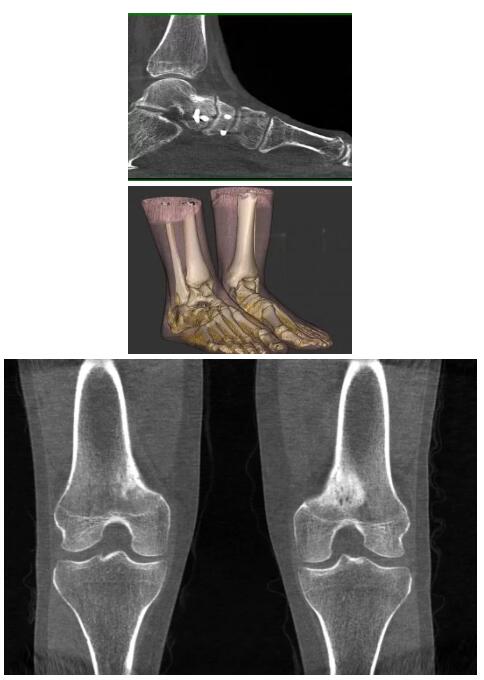

比如上面這款專用于足部和踝部掃查的CT成像系統(tǒng),患者在進行CT掃查時只需要站在上面即可,雙腳站或者單腳站都可以,當(dāng)然,如果患者不是那么方便站著做完CT掃查,也可坐在上面。

這款CT掃查系統(tǒng)自帶屏蔽裝置,它的體積非常小,僅需要極小的空間即可,并不像常規(guī)CT那樣需要一間單獨的檢查室。此外,這種CT掃查的速度非常快,僅需30秒左右可以完成檢查,輻射劑量相對常規(guī)的CT要少許多,尤其適合醫(yī)院的骨科使用。

而患者站著做足部或者踝部做CT檢查還有個好處是,可以檢查患者在負(fù)重的情況下,骨關(guān)節(jié)的真實情況,而躺著做CT掃查時未必能看出來。負(fù)重CT掃查特別是對于受傷的運動員或者舞蹈員來說意義更大,能夠更準(zhǔn)確地評估傷情,幫助他們盡早復(fù)原。

以下是這些“特立獨行”的CT所拍出來的圖像: